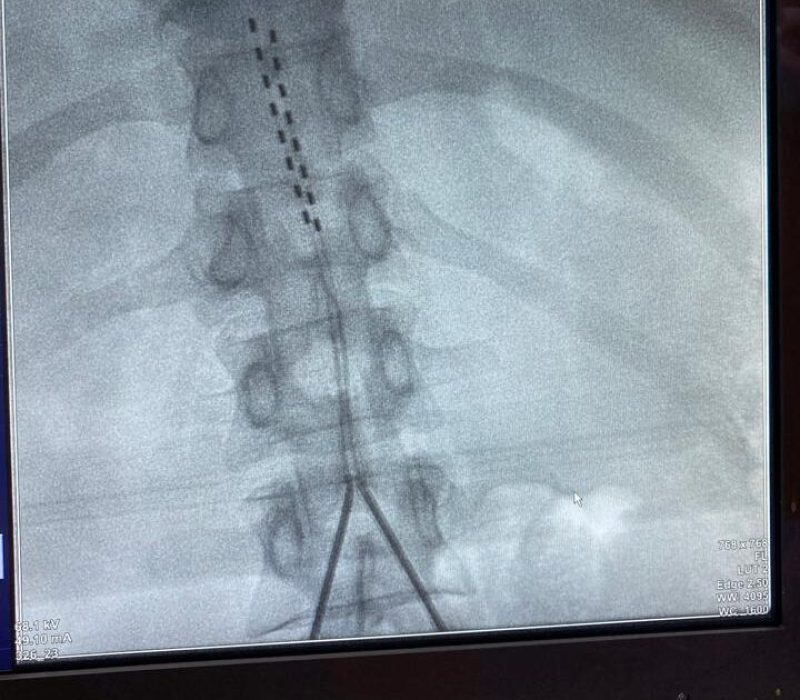

Los estimuladores de la médula espinal constan de cables delgados (los electrodos) y una pequeña batería similar a un marcapasos (el generador). Los electrodos se colocan entre la médula espinal y las vértebras (el espacio epidural) y el generador se coloca debajo de la piel, generalmente cerca de las nalgas o el abdomen.